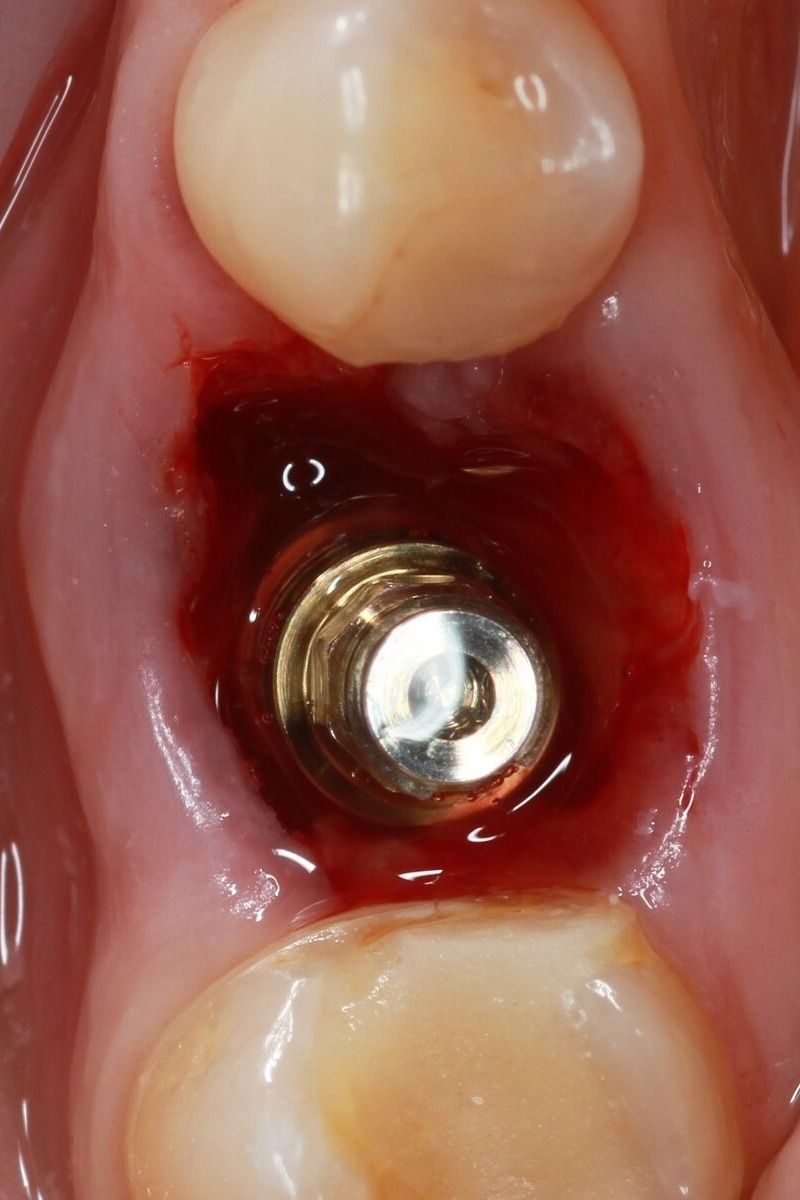

Implant installation

• we remove teeth, agreed in the treatment plan.

• if necessary, we perform bone and gingival grafting

• we install implants

Installing the healing abutment

We install the gingiva former for 2-3 weeks in order to obtain an aesthetic gingival margin for subsequent prosthetics.